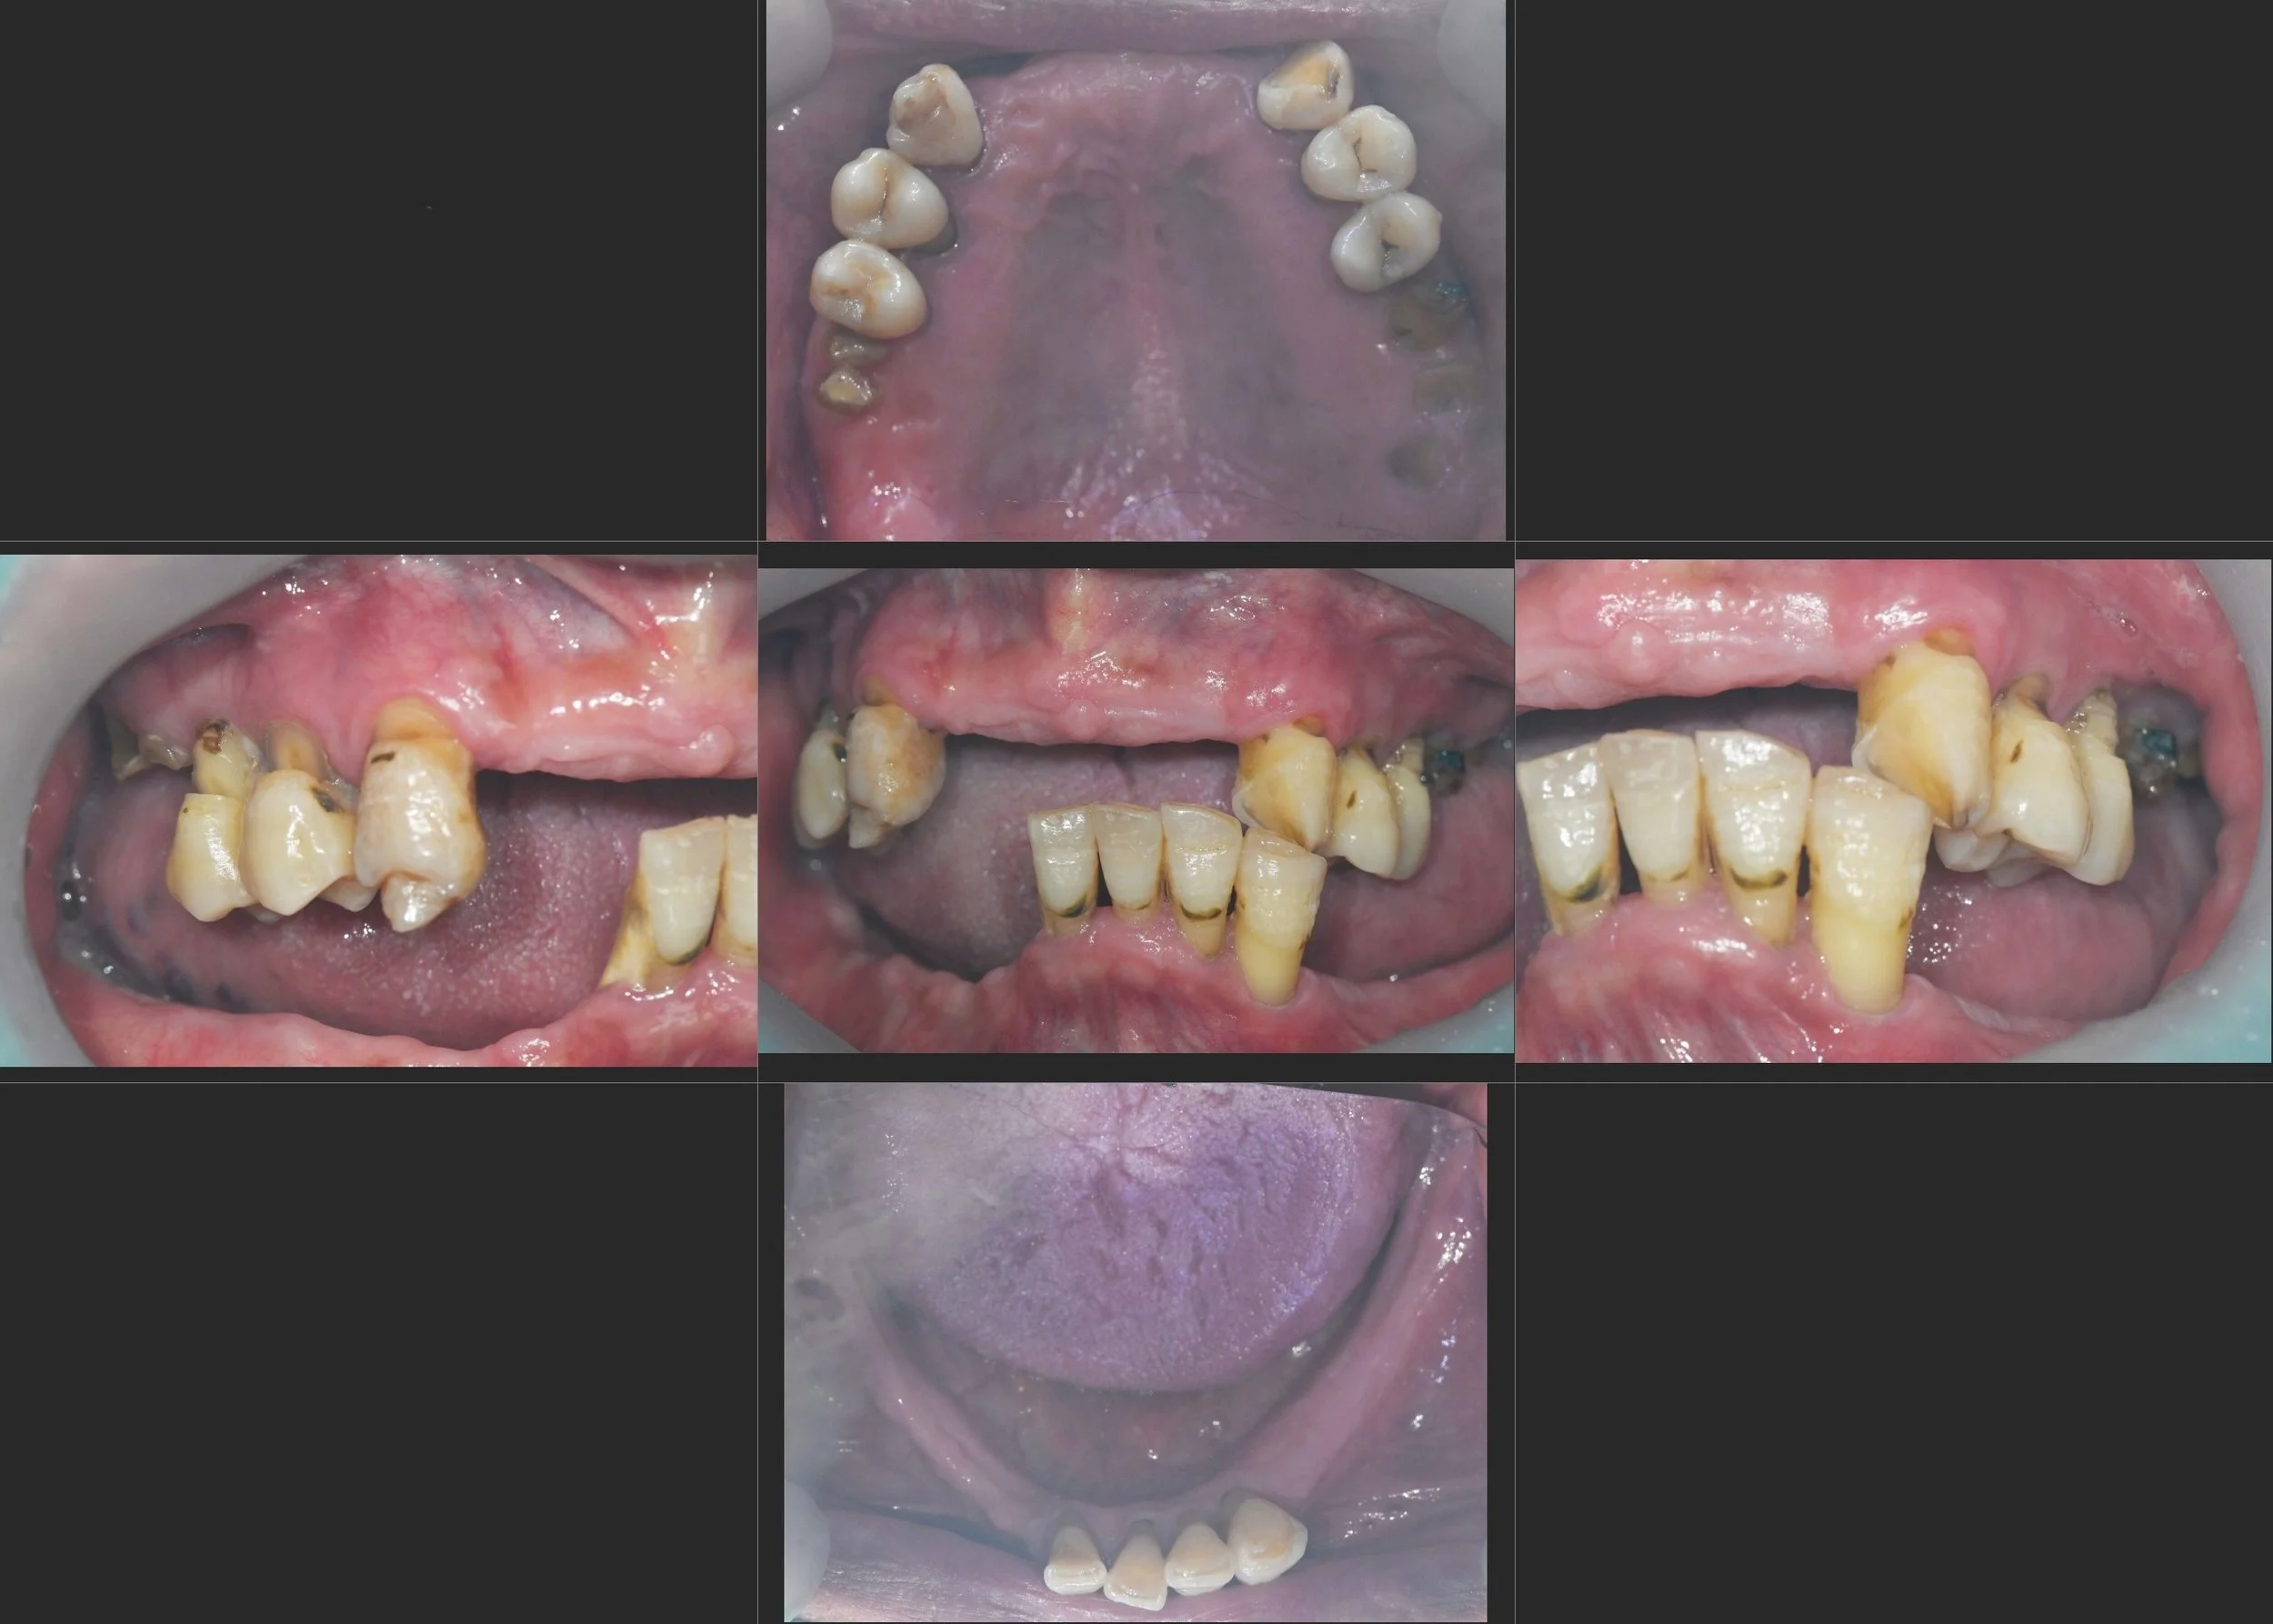

38. Comprehensive Full-Arch Reconstruction: Reversing the Domino Effect of Tooth Loss

Management of Generalized Severe Periodontitis and Posterior Bite Collapse in a Female Patient in her 60s. A Systematic Approach to VDO Recovery and Strategic Esthetic Rejuvenation.